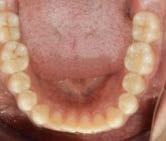

Figura 2. Fotografías oclusales y ortopantomografía. A. Vista de la arcada superior. B. Vista de la arcada inferior. C. Ortopantomografía.

El objetivo de analizar estos conceptos es presentar un caso clínico de paciente masculino de 10 años, clase II división 2, con mordida profunda empleando aparatología ortopédica de Simoes Network y de Pistas Planas.

Reporte de caso clínico

Paciente masculino de 10 años, se presenta a la consulta en la clínica Gnathos, la mamá reporta desagrado en la estética dental y facial del paciente. En la exploración clínica se observa mordida profunda, amplio número de piezas dentales con caries, fracturas dentales, mala higiene y encías inflamadas. presenta clase II división 2, se le indicaron estudios complementarios para diagnóstico asertivo, modelos de estudio,